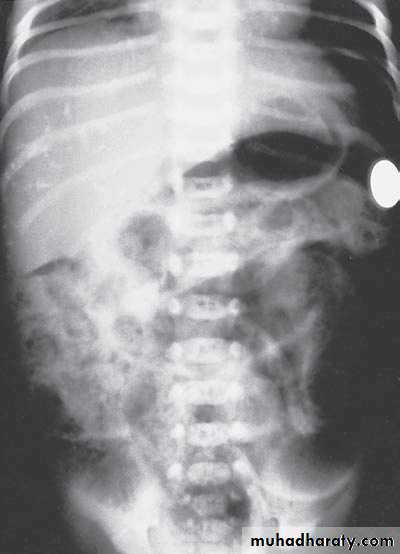

Bowel Obstruction

first photo upper bowel obstruction // second photo lower bowel obstructionDescription:

double bubble signCauses of obstruction in the first photo:

1- duodenal obstruction2- duodenal atrasia

3- annular pancreas

4- mal-roation of bowel

Cardinal symptoms of bowel obstruction (first photo):

1- mild abdominal distention (epigastric distention)2- failure if pass of meconium

3- bile stain vomiting

Note:

In pediatric we cannot say small or large bowel obstruction but we say upper

or lower bowel obstruction